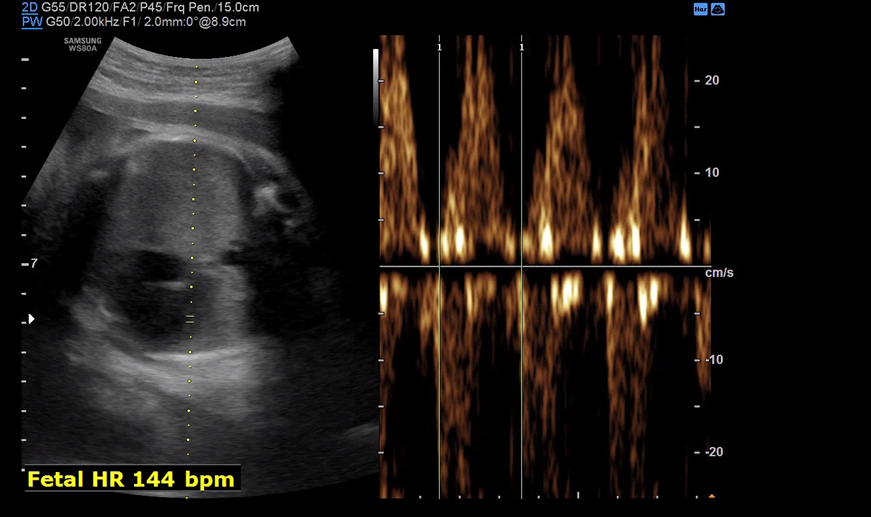

막달 검사를 마치고 30분 정도 대기한 뒤 원장을 진료를 봤다. 4분가량 배 초음파로 아기의 상태를 체크해주시는데 BPD, Fetal HR, AC, FL 순서로 봐주시고 마지막으로 아기 얼굴을 보여주셨다.

지난번 진료에는 잘 못 먹고 체중도 늘지 않아서 아기도 딱 400g 체중이 증가했지만 주수에 비해 좀 작은 편이었는데 이번에는 잘 먹고 내 체중도 늘어서 갔더니 아기도 폭풍 성장해있었다. 원래 주수에 비해 작아서 예정일까지도 채울 수 있을 거라 생각했는데 이대로면 좀 더 일찍 나올 수 있다고 하셨다. 급 당황.